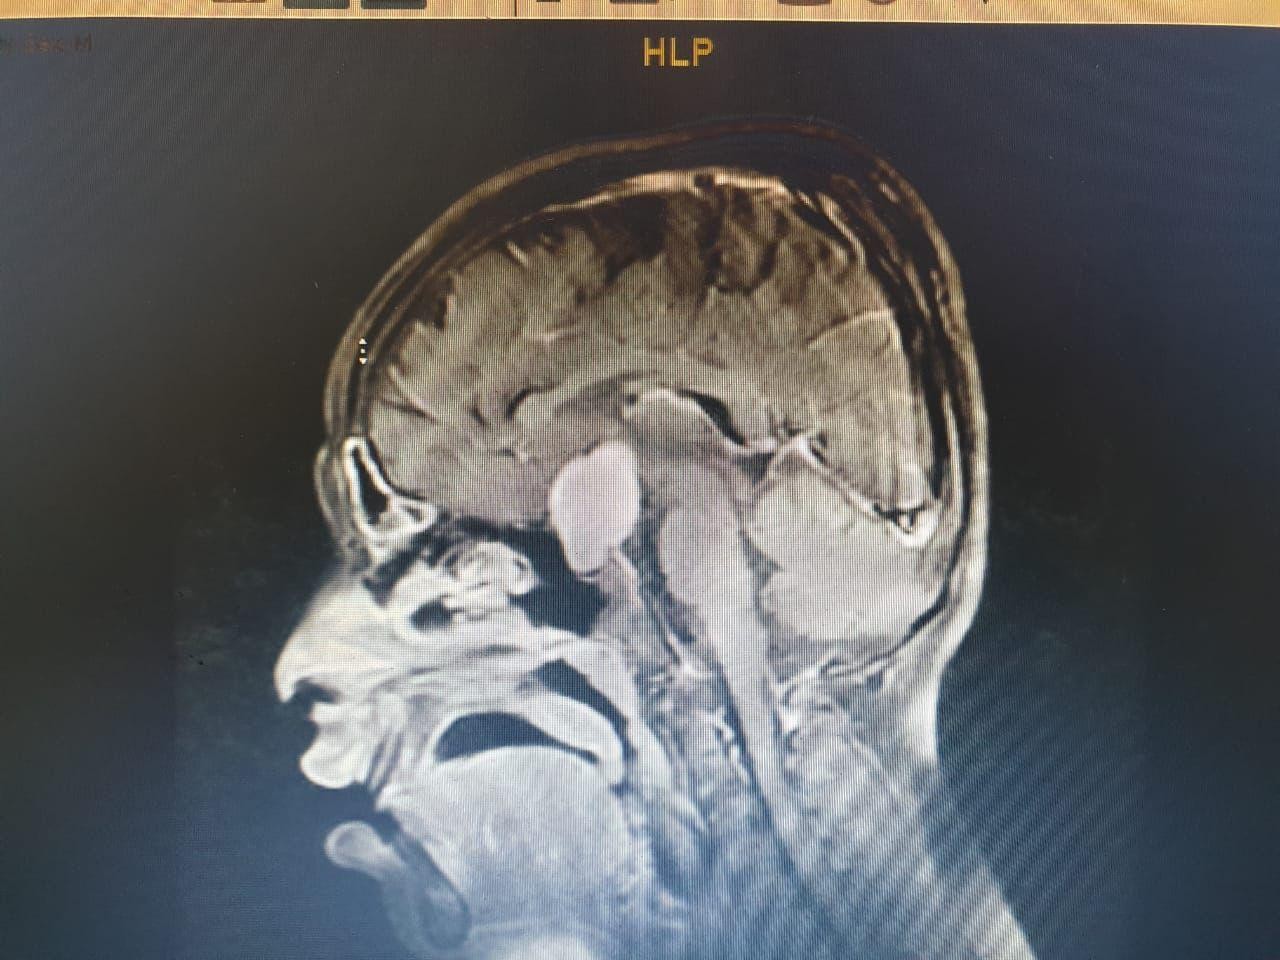

وعلى الفور أجرى الفريق فحوصات متقدمة ، واتضح وجود"ورم" بقاع الجمجمة ، ومتصل بالغدة النخامية.

وأشار المتحدث الرسمي بصحة الطائف سراج الحميدان ,أن الفريق الجراحي للمخ والأعصاب ، تدخل جراحيا بعملية استمرت 7 ساعات لإزالة الورم بالرغم من خطورة الوضع ، وتكللت بالنجاح بفضل الله .